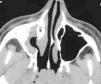

La exploración clínica fue normal. No se observó tumefacción ni palidez de la mucosa nasal. Tampoco se apreciaban asimetrías faciales. La exploración endoscópica nasal revelaba un discreto desplazamiento lateral de la apófisis unciforme. Los resultados de prick-test fueron negativos. La radiografía de tórax no mostraba alteraciones patológicas. En la radiografía de senos paranasales se apreciaba una ocupación completa del seno maxilar derecho, por lo que fue diagnosticada de sinusitis maxilar, y se le pautó tratamiento antibiótico. En la radiografía realizada 2 semanas más tarde se mantenía la imagen de ocupación, por lo que se decidió realizar una TC, en la que se apreciaba una opacificación parcial del seno maxilar derecho, con desplazamiento lateral de la pared infundibular medial, con incipiente descenso de la pared orbitaria inferior y retracción de la mucosa del meato medio, sin niveles hidroaéreos endosinusales (figs. 1 y 2). Dada la ausencia de signos, síntomas y complicaciones, la actitud terapéutica ha sido expectante. Si se produjera una evolución hacia el enoftalmos, se propondría tratamiento quirúrgico dirigido a la liberación del ostium del seno maxilar.

Figura 2.TC de senos paranasales (proyección axial). En esta imagen se aprecia la retracción de la mucosa sinusal, el menor tamaño del seno maxilar derecho, así como la incipiente retracción ósea.

Los criterios diagnósticos radiológicos de ACM incluyen opacificación del seno maxilar, desviación lateral de la pared infundibular medial y retracción de la mucosa sinusal 3-5,9-11. Estos criterios están presentes en el caso que aportamos (figs. 1 y 2).